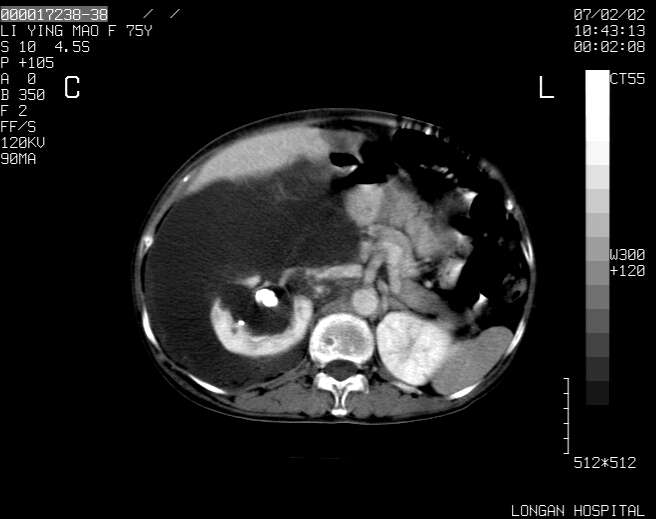

以下是引用dyqct在2007-2-10 8:53:00的发言:[br]考虑:1、肝脏多发囊肿[br] 2、左肾囊肿,右肾多发结石并积水。[br] 3、右胸少量积液。[br] 4、右肾周包裹性积液或淋巴管瘤(有见缝就钻的征象、薄隔、小结节状钙化)?[br] 5、腰椎动脉瘤样骨囊肿?[br] [br] [br]